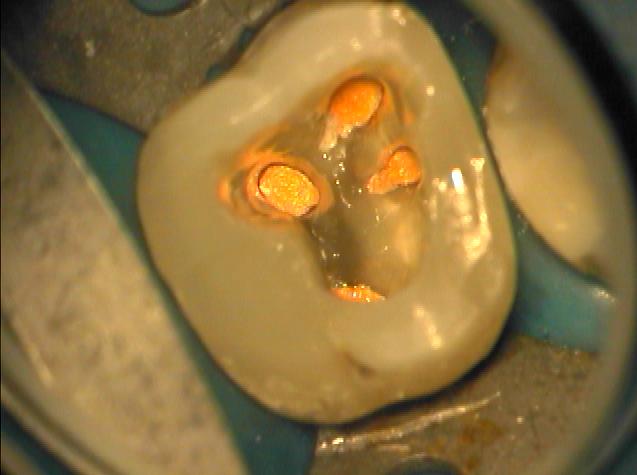

Klinische Situation nach abgeschlossener Aufbereitung

Vergrößerte Situation

Vergrößerte Situation; deutlich sind die 4 Kanaleingänge zu erkennen